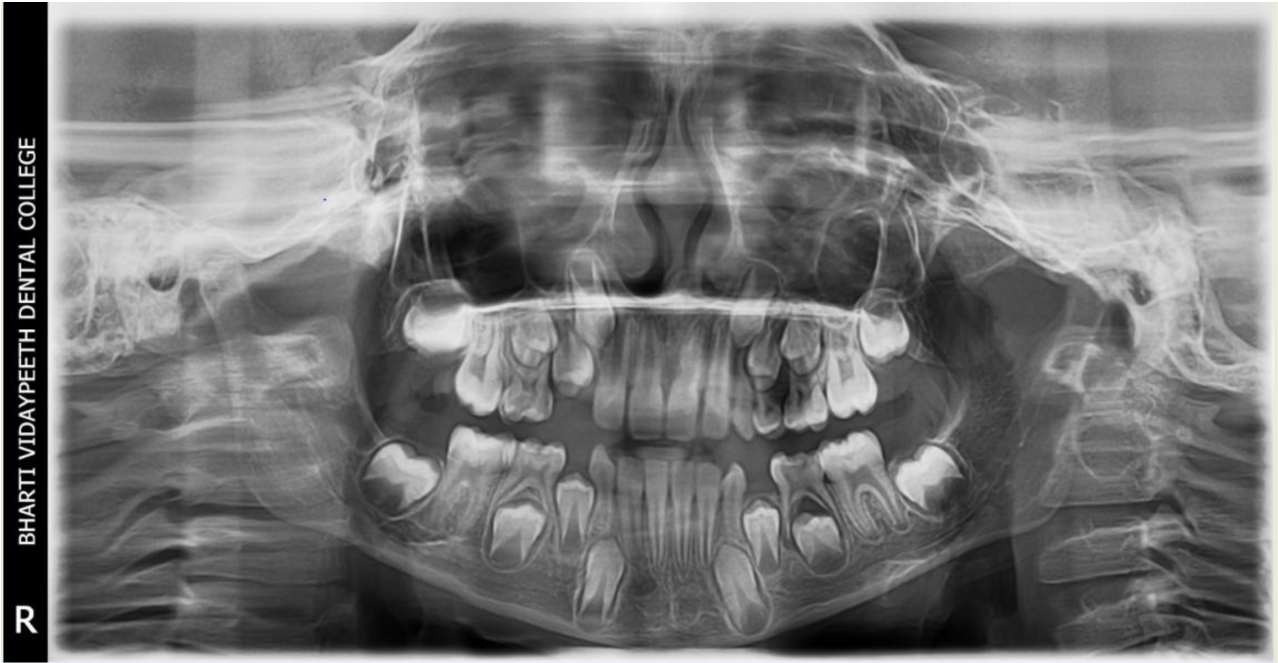

A nine year old boy reported to the Department of Pedodontics and Preventive Dentistry of Bharati Vidyapeeth Deemed University, Sangli with a chief complaint of pain and abscess in the lower left back region of the jaw since one month. Patient was a known case of autism spectrum disorder. He was inattentive, hyperactive and showed repetition of gestures. Psychological testing report showed childhood autism rating scale (CARS) 2, which falls into mild to moderate autistic category. Vineland social maturity scale (VSMS) measuring the social intelligence of child was found to be 31.5 with social age of around 5-6years. The family history was non-contributory. He was not on any medications and had reported no history of drug allergies. Extra-oral examination showed no specific findings (Figure 1). Intraoral examination revealed multiple carious lesions (Figure 2) (Figure 3). Occlusal caries involving enamel, dentin and pulp with 55 and 75. Intra oral dentoalveolar abscess was also seen in relation with 75 (Figure 4). Dentinal caries was seen with 85 and occlusal pit and fissure caries was seen with 65. No soft tissue abnormalities were appreciated. Radiographic evaluation by orthopantomogram was also done which revealed no abnormality (Figure 5). It was difficult for the patient to co-operate on the dental chair and understand the instructions given to him; hence treatment was planned under general anaesthesia. A complete pre anaesthetic evaluation was done and the patient was categorized under ASA II. Treatment plan was explained to the child’s parents and a written consent was obtained from them. The dental treatment done under general anaesthesia included pulpectomy of 55, 75 with glass ionomer cement restoration followed by placement of pre trimmed and pre contoured stainless steel crowns (Figure 6) (Figure 7). Glass ionomer cement restorations were done in 65 and 85 and pit and fissure sealants application on 16, 26, 36 and 46. Post-operative orthopantomogram showed well placed restorations and crowns (Figure 8). Patient’s post-operative recovery was uneventful. Treatment rendered reduced the pain and discomfort.Oral hygiene care instructions were given to the parents and maintenance protocol was explained and they were also encouraged for regular follow-up for preventive dental care. The two months follow-up revealed improved eating habits of the child.

Figure 5 Pre-operative orthopantomograph.